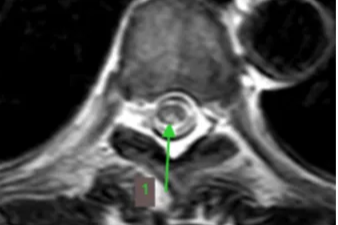

为她,打赢这场头脑保卫战!